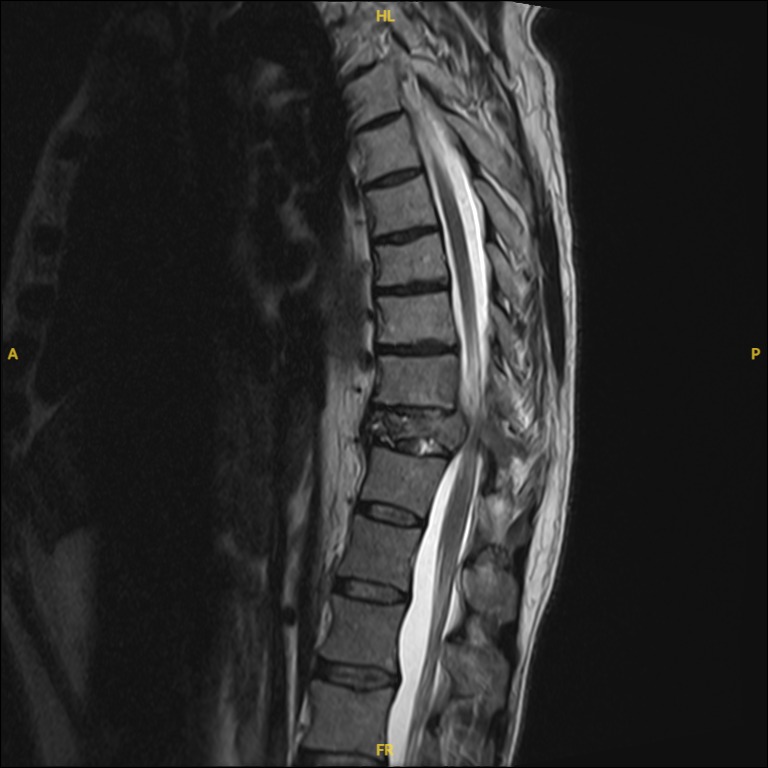

1. Pre-Surgical Evaluation: Includes imaging studies (MRI, CT, or X-rays), biopsy (if needed), and a thorough assessment of overall health.

Spinal tumors are abnormal growths that develop in or around the spinal cord or vertebrae. They can be classified as:

– Malignant Tumors: Cancerous growths that may originate in the spine or spread from other areas of the body (metastatic tumors).